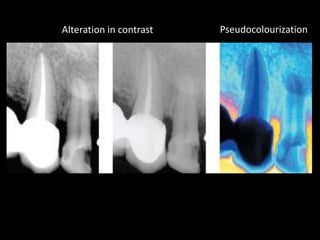

4. Digital radiography provides advantages like automated measurements and image manipulation but has higher initial costs and bulkier sensors.